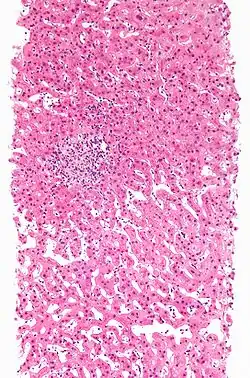

Drug-induced hepatitis with granulomata. Other causes were excluded with extensive investigations. Liver biopsy. H&E stain.

Drug-induced hepatic granulomas are usually associated with granulomas in other tissues and patients typically have features of systemic vasculitis and hypersensitivity. More than 50 drugs have been implicated.

Causes:

Allopurinol, phenytoin, isoniazid, quinine, penicillin, quinidine